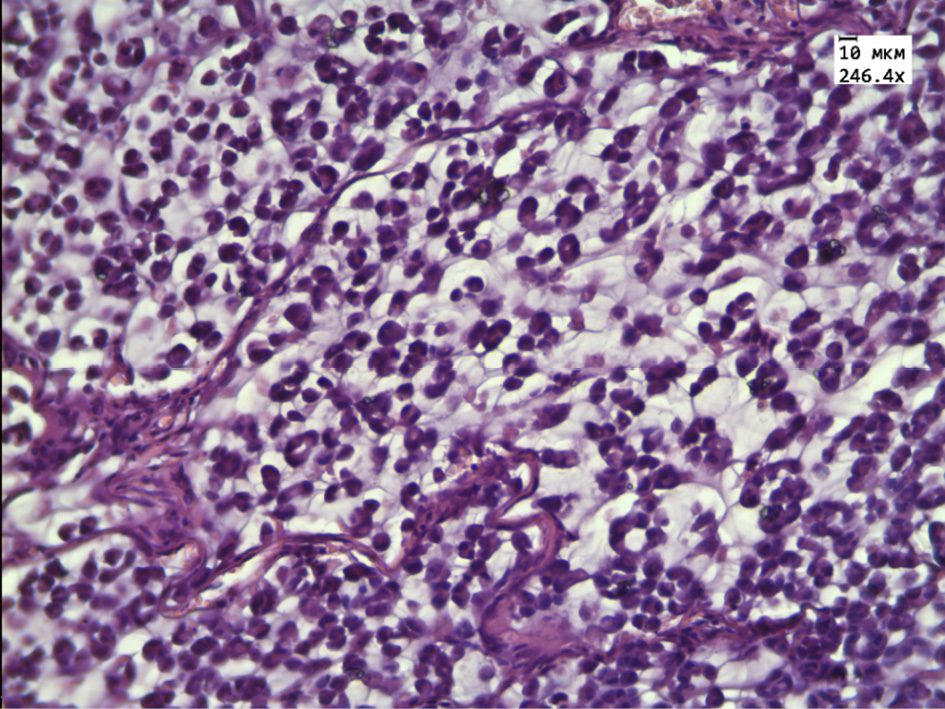

During the morphological and morphometric study of the tumor tissue in the rats group receiving alcoholic thyme extract, attention was paid to the pronounced pathomorphosis mainly in the central parts of the tumor. A large number of “shadow cells”, a decrease in the size of tumor cells, and extensive zones of necrosis were noted. The intact tumor cells are represented by small rounded cells with rounded or bean shaped nuclei with single small vacuoles containing mucus. The tumor cells are located in cells formed by thickened connective tissue partitions with a large number of thin-walled blood vessels. Connective tissue fibers are infiltrated by lymphocytes. Mitosis was determined only in one case of observation (Fig. 2).

Figure 2 – Histological structure of the transplanted hepatic cancer in the group receiving alcohol extract of Thymus marschallianus Willd.

Note: dystrophic and necrotic changes in tumor cells, “shadow cells” (black arrow), thickening of connective tissue partitions (white arrow). Stained with hematoxylin and eosin. Magnification 246.4×.